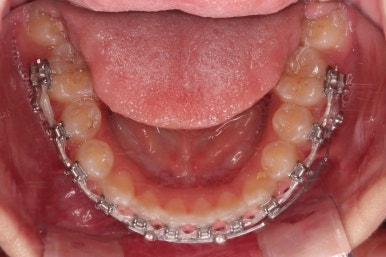

아랫니도 바로 교정장치를 부착하고, 교정장치를 통해 윗니와 아랫니를 끌어주고 철사를 이리저리 디자인해서 힘을 주고, 다양한 부가적인 부착물들을 활용하기로 했어요.

어떤 장치가 중간중간 활용되고 있는지는 틀린그림찾기처럼 찾아보시길 바랍니다😄

과개교합, 옥니, 앵글씨 2급 부정교합 모두 좋아지고 있어요.

앞니 각도가 매우 좋아졌고요.(옥니 개선) 위아래 앞니가 덮는 정도도 개선이 되었어요.(과개교합, 딥바이트)

엉성했던 어금니 맞물림도 매우 좋아졌어요.(앵글씨 2급 부정교합 개선)